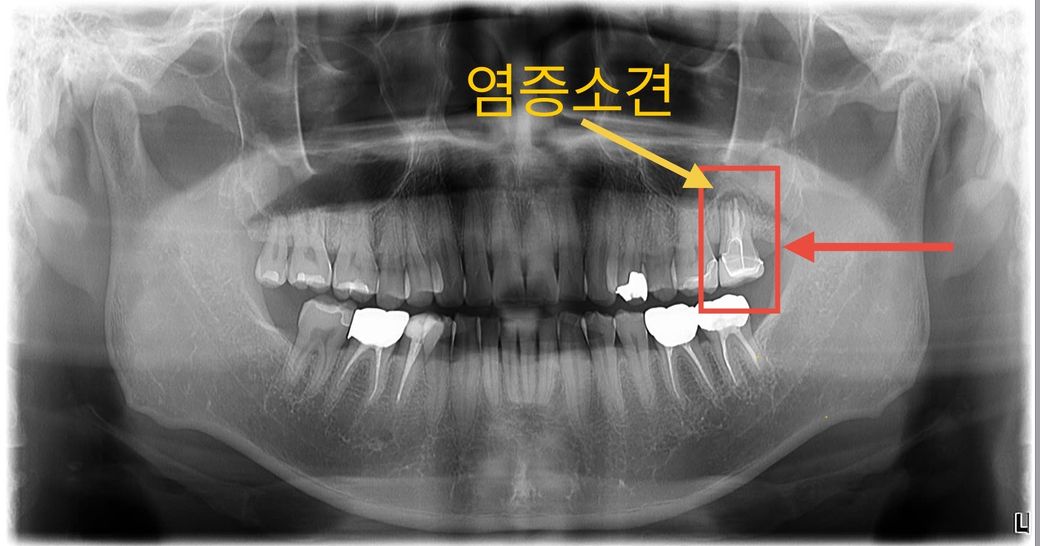

1) 엑스레이상 가장 안쪽 어금니쪽 잇몸에 염증이 보인다.

1. 빨간네모 - 좌측 위 문제의 어금니 (*현지 치과에서 찍은 엑스레이사진)

2. 바깥쪽 잇몸은 크게 내려앉지 않았음.

3. 안쪽 잇몸은 10여년전 했던 크라운보다 많이 내려옴. (*현지 의사의 의견은 치아가 검게 된 것은 현재의 통증과 크게 관련은 없다고 하였습니다.)